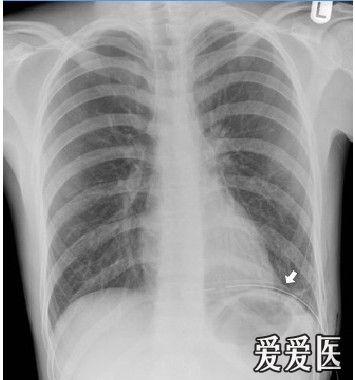

气胸影像图片,气胸胸片典型图片

呼吸版经验交流(7)气胸:影像学解读指南

关于气胸的x光片